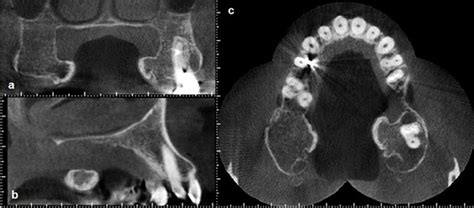

• Torus Palatinus: These occur on the roof of the mouth (hard palate), usually in the center. They can range from flat and wide to lobulated and prominent.

• Torus Mandibularis: These appear on the lingual (tongue-side) aspect of the lower jaw, usually above the mylohyoid line. These are often bilateral, meaning they appear on both the left and right sides of the lower jaw.